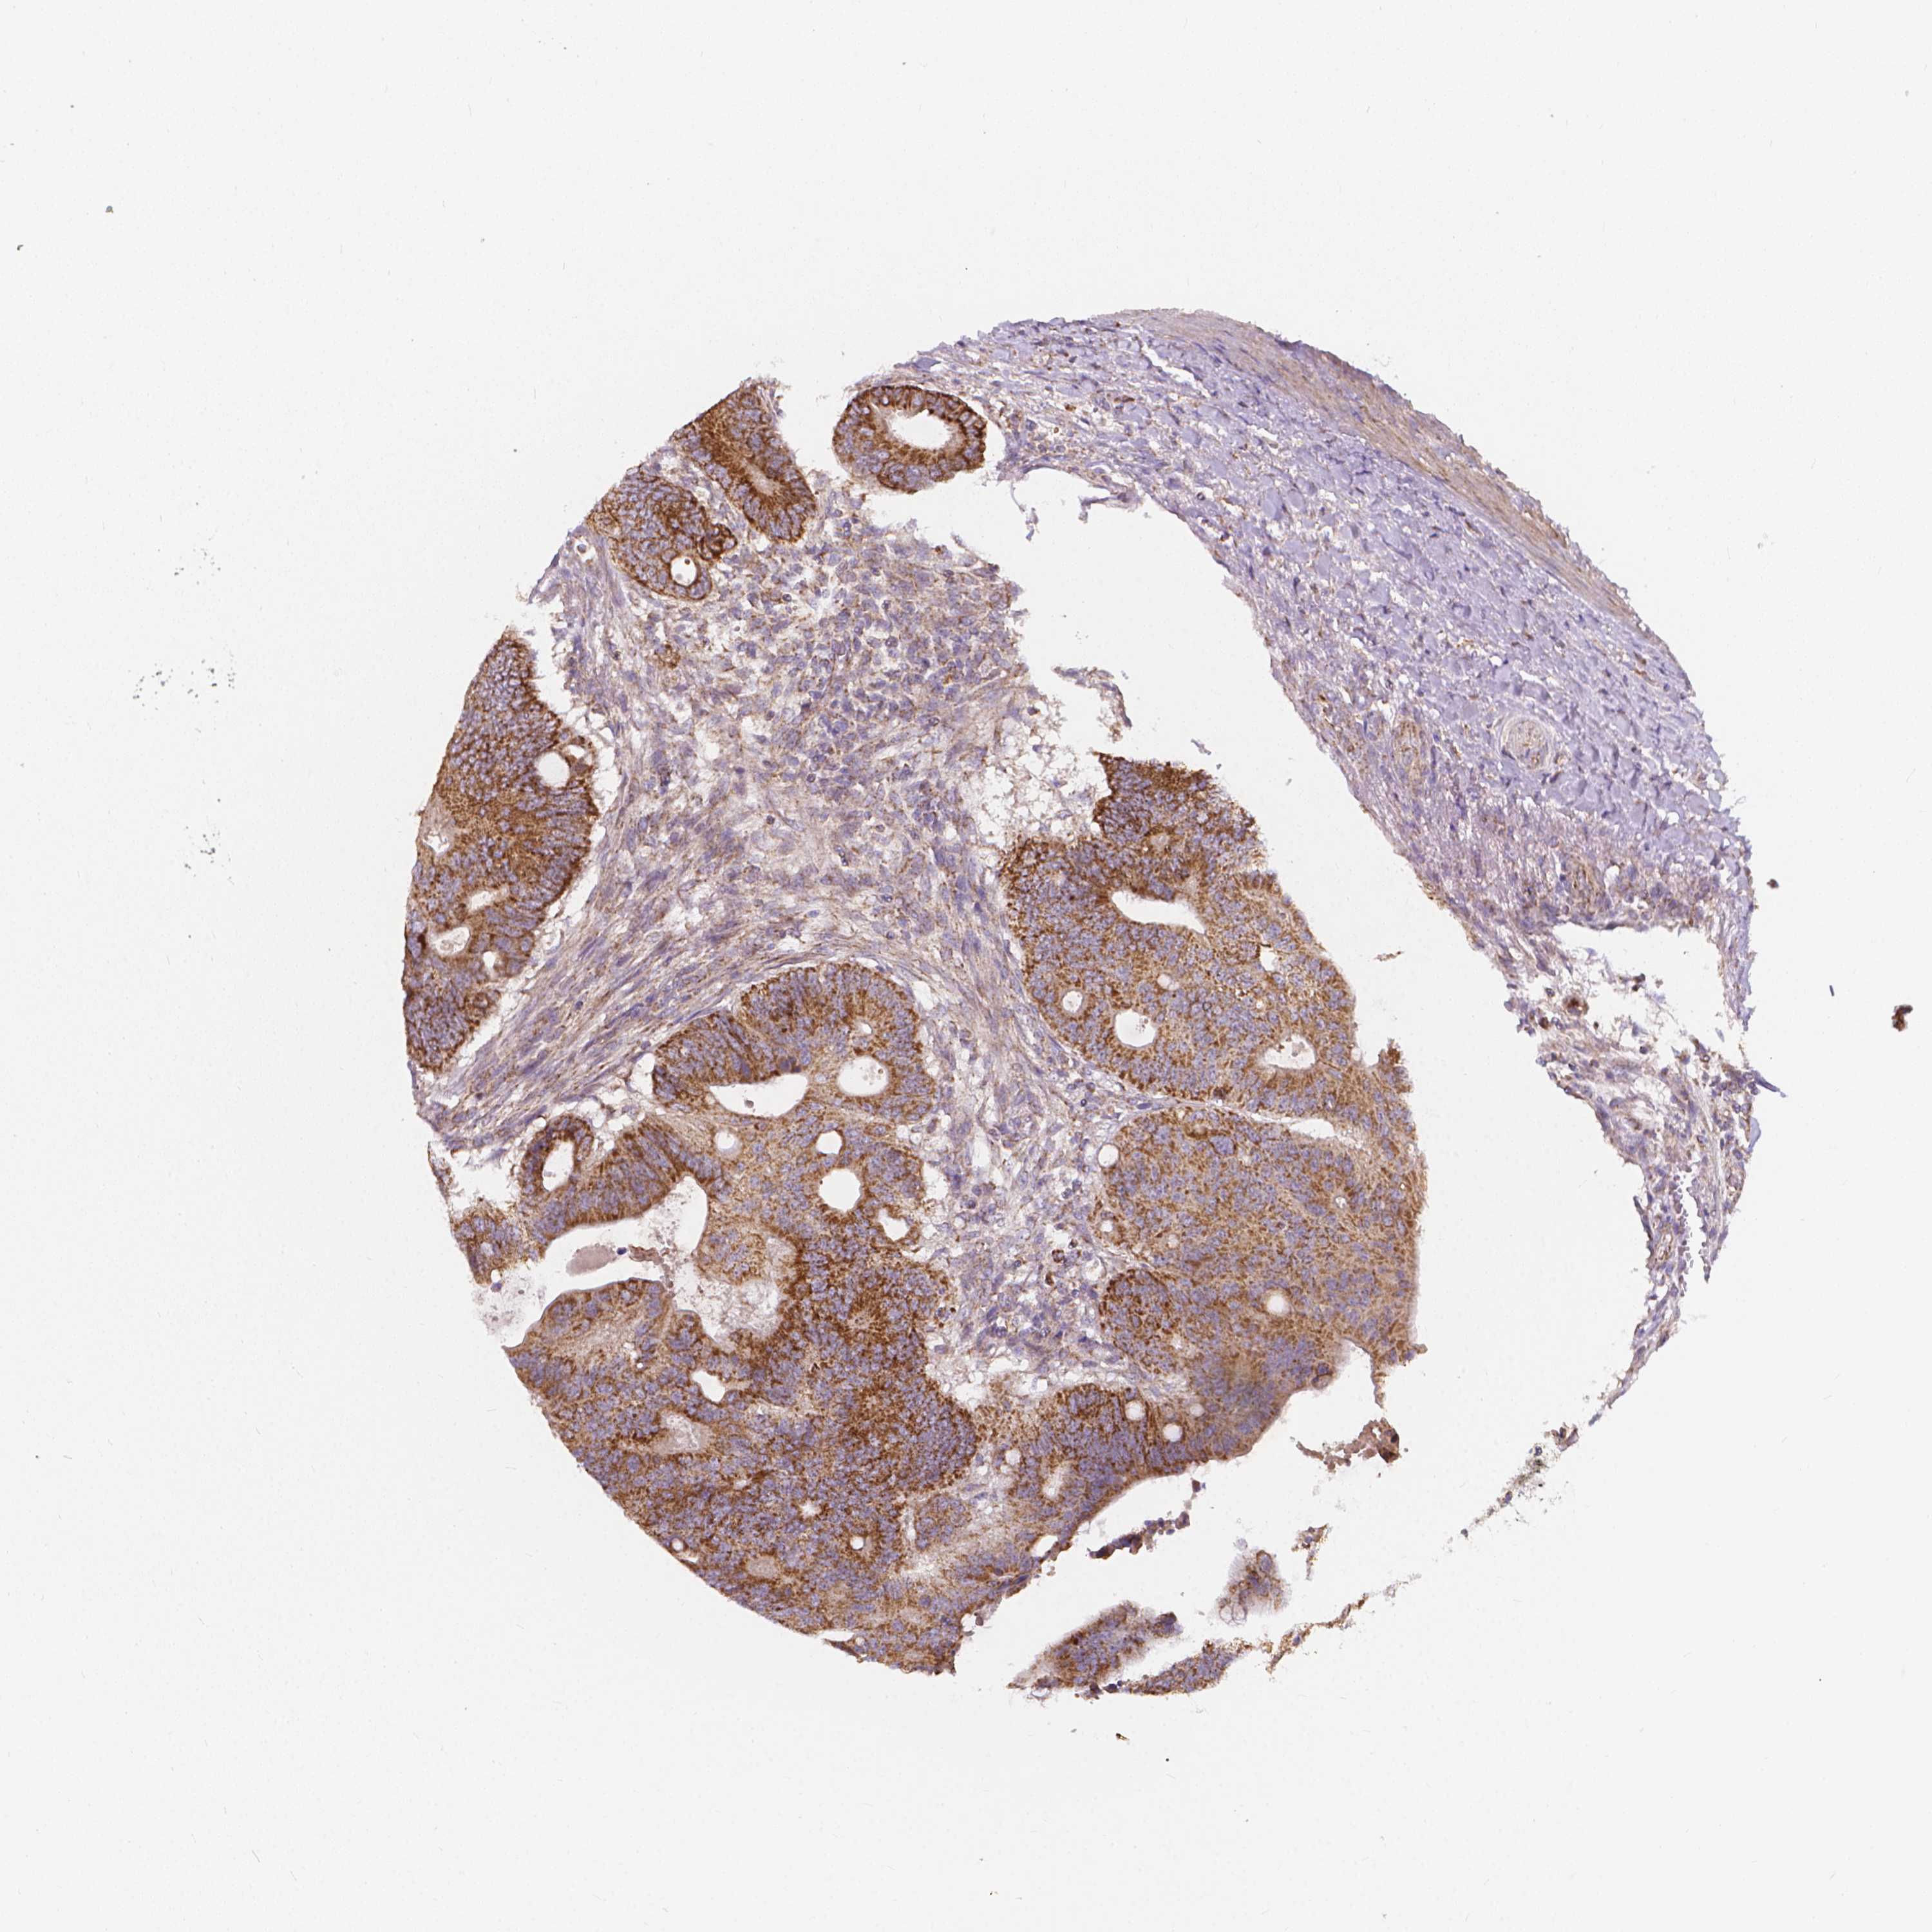

CANCER COLORECTAL CANCER Show tissue menu

Colorectal cancer

Colon adenocarcinoma